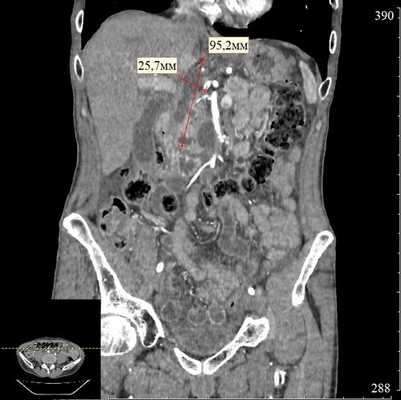

При эндосонографии (эндоУЗИ) в области головки поджелудочной железы визуализировано анэхогенное образование с четкими неровными контурами неправильной продольной формы, размерами 3,1х10 cм, прилежащее к воротной вене - постнекротическая киста с преимущественно внеорганным расположением (рис. 3).

Риски и особенности ситуации

К особенностям ситуации нужно отнести крупный размер и сложную конфигурацию кисты, ее преимущественно внеорганное расположение и близость воротной вены. Для того чтобы оценить пространственное соотношение кисты с прилежащими анатомическими структурами, а также определить наилучшее место для дренирования, была проведена 3D виртуальная компьютерная реконструкция (рис. 4).

Через 3 месяца после операции при контрольной КТ отмечена полная ликвидация кисты поджелудочной железы (рис. 8). В связи с этим стент, полностью выполнивший свою функцию, был удален.